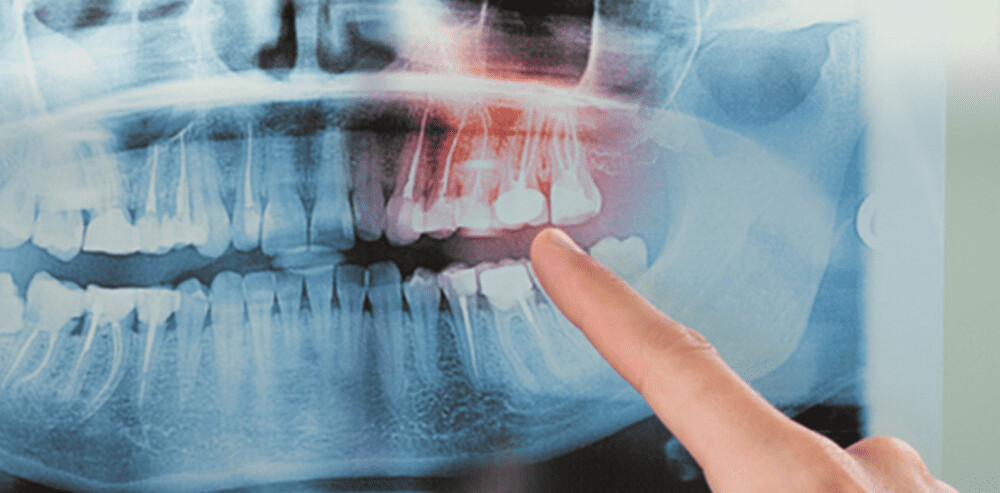

Your doctor or dentist will probably feel your head and neck for any signs of an unusually long styloid process. They may also use an X-ray or CT scan to see your styloid process and stylohyoid ligament in better detail.

An impacted tooth is one that has been blocked from emerging from the gums and is often discovered during a dental X-ray. Some impacted teeth will eventually break through the gums without treatment; also, removing baby teeth or orthodontic treatment can sometimes allow the teeth to come in properly. Other times, tooth extraction is necessary if the teeth are unable to erupt through the gums on their own. Often, surgical extraction is used on wisdom teeth or maxillary canines that cannot be guided to the correct position.